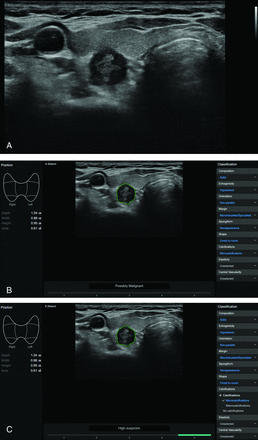

The S-Detect 2 CAD system integrated into a commercially available US system was used to collect CAD data by the same radiologists. On the transverse image plane, an ROI was manually drawn around the target nodule.10,11,16 The CAD system automatically outlined the contours of the mass and assessed the US features: composition (solid, partially cystic, or cystic); echogenicity (hyperechoic/isoechoic or hypoechoic); orientation (parallel or nonparallel); margins (well-defined, ill-defined, or microlobulated/spiculated); spongiform status; shape (ovoid to round or irregular); and calcifications (none, microcalcification, macrocalcification, or rim calcification). Finally, the CAD system provided a possible diagnosis using the TIRADS classification (based on the K-TIRADS and the ATA-TIRADS) or a dichotomous outcome classification (possibly benign/possibly malignant) (Fig 2).13,14

A US image of a thyroid nodule acquired with the S-Detect 2 CAD system. A, A solid hypoechoic nodule with suspicious US features is evident in the right thyroid gland. B and C, The CAD software automatically calculates the mass contours (green contour) and presents the US features on the right of the screen and a diagnosis based on the dichotomous outcome and TIRADS classification on the bottom.